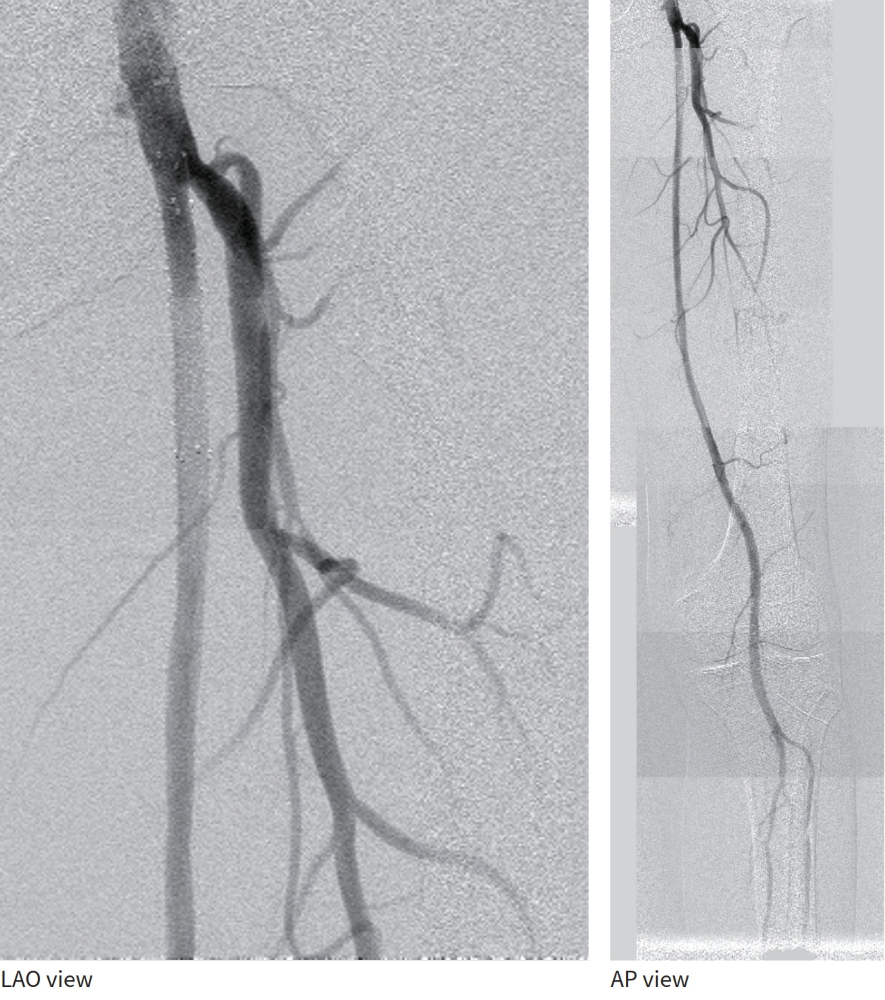

- プラークをフルカバーするため、SFA起始部にバイアバーン® ステントグラフト径6.0/長50 mmを追加留置(図4)。

- 径6.0/長150 mm高圧バルーンにて高圧拡張を追加し、DFAの血流も問題がないことを確認して手技終了(図5)。